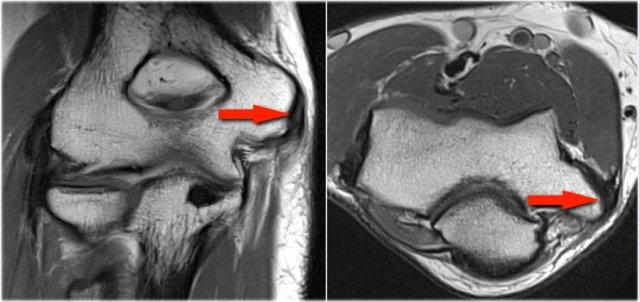

Plica

Cấu trúc này ở phía bên ngoài của khớp đôi khi được nhìn thấy và là một nếp gấp hoạt dịch (plica).

Nó có thể nổi bật và trông gần giống như một sụn chêm.

Đây là một cấu trúc bình thường, nhưng đôi khi nó bị dày lên hoặc không đều và có thể là nguyên nhân gây ra các triệu chứng.